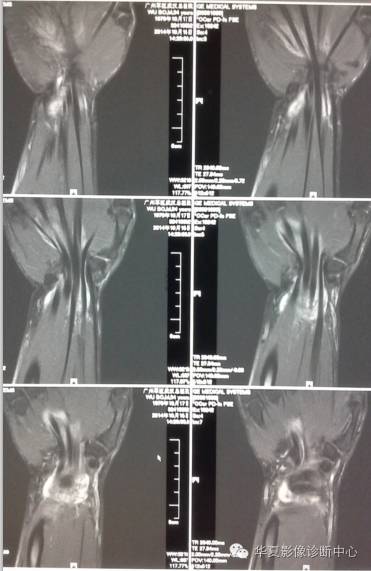

MRI影像表现:1.掌侧环状韧带膨出;2.正中神经受压水肿,体积大,T2高信号;3.伴发表现:腱鞘炎、滑膜囊肿等。